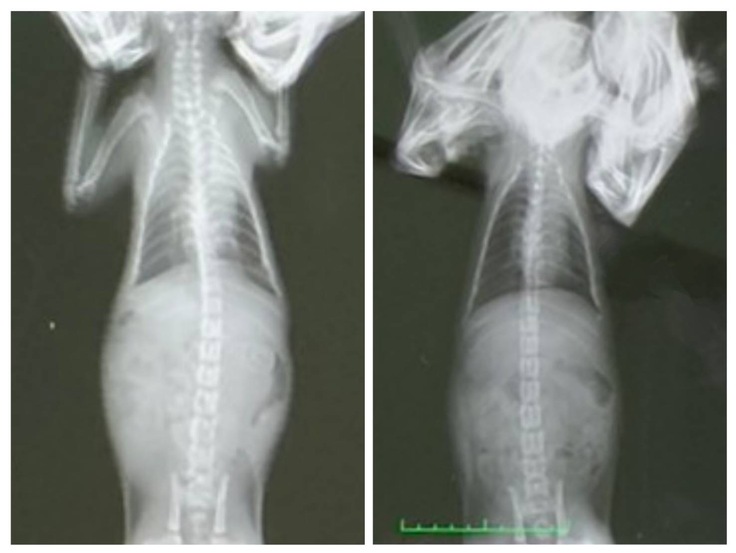

ヤマトは先週、左肺の一部が無気肺かもしれないと言われ、新しい薬を処方していただいておりました。そのおかげもあり、真っ白だった部分がうっすらとした白にまで回復しました!また最近、食欲が増し体重が増えたことも良くなっている要因ではないかと言われました。

今回は追加で5日間、同じ薬を処方されました。薬は飲み切り次第一旦中断し、約10日後に再度通院となります。通院時にはナイトも薬をやめて2週間ちょっと経つことになるので、経過観察としてレントゲンを撮ってもらいに行く予定です。